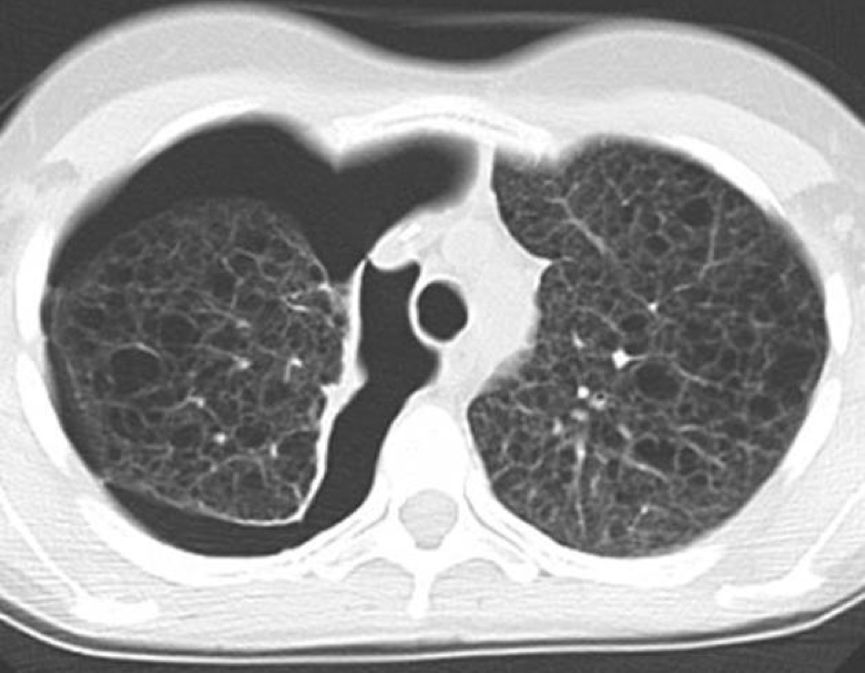

外院肺功能检查提示:阻塞性通气功能障碍。HRCT显示双肺弥漫性分布类圆形薄壁囊状阴影,囊壁较光滑,囊腔大小不等,多数在2~10 mm之间,右侧胸腔内见气体影。纵隔结构清楚,未见肿大淋巴结。

常规CT表现为两肺密度减低,体积增大,呈肺气肿样改变。HRCT对本病的早期诊断及病情发展的监测有重要意义,其特征性改变为两肺广泛弥漫性分布的薄壁小囊状病变,两侧对称,无上中下肺野的区别,也无中央性与周围性的分布差异。囊腔直径为2~30 mm,大多数直径小于10 mm,囊壁厚度多小于2 mm。